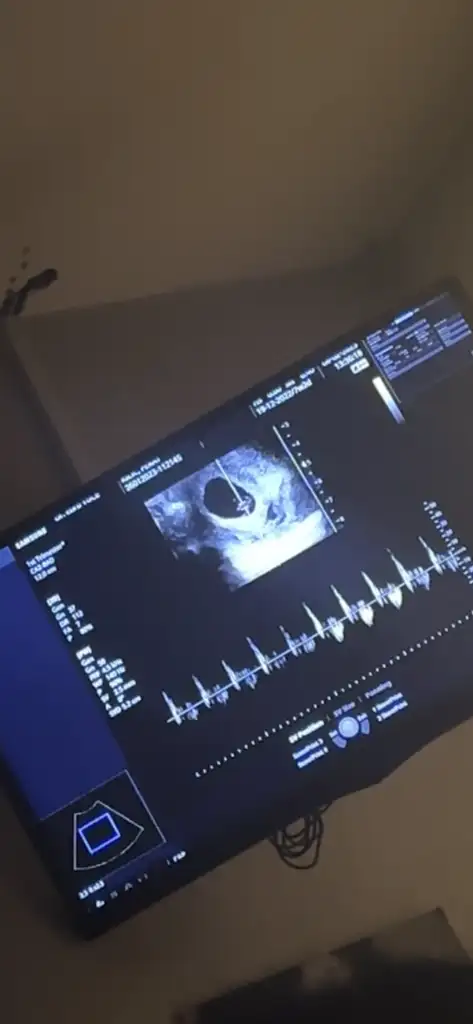

Merhaba millet

Ramzi teorisine göre cinsiyet tahmini yapacagim ilk ultrasyon resminizi atin bakiyim. Eger cinsiyetiniz belliyse hic söylemeeyin bakalm dogru tahmin edebilecekmiyim daha dogrusu ramzi teorisi hakli cikacak mi?

Sizce benim nedir kız gibi dedi ama fikriniz

Eklentiler

• 3C82ED27-2FAC-4521-AC99-75F204A4E937.webp

3C82ED27-2FAC-4521-AC99-75F204A4E937.webp

73,9 KB · Görüntüleme: 95

Kemik yapısı erkeğe benziyor ama ben 6-7-8 haftalık ultrason resmiyle ramzi teorisine göre yorum yapıyorum. Varsa o haftalarda resmi onu atın lütfen☺️